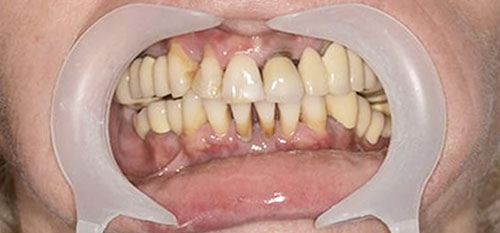

„All-on-4“ yra pažangi dantų implantavimo technika, leidžianti atkurti visą viršutinio arba apatinio žandikaulio dantų lanką vos su 4 implantais. Ant šių implantų fiksuojamas nuolatinis dantų protezas, kuris užtikrina ne tik estetišką šypseną, bet ir pilnavertę kramtymo funkciją. Šis metodas yra greitas, komfortiškas ir daugelio specialistų pripažįstamas kaip vienas efektyviausių sprendimų bedančiams žandikauliams netekus daugelio ar visų dantų.

- Išsaugosite žandikaulį, taisyklingą sąkandį ir drąsiai šypsositės. Valgysite be apribojimų.